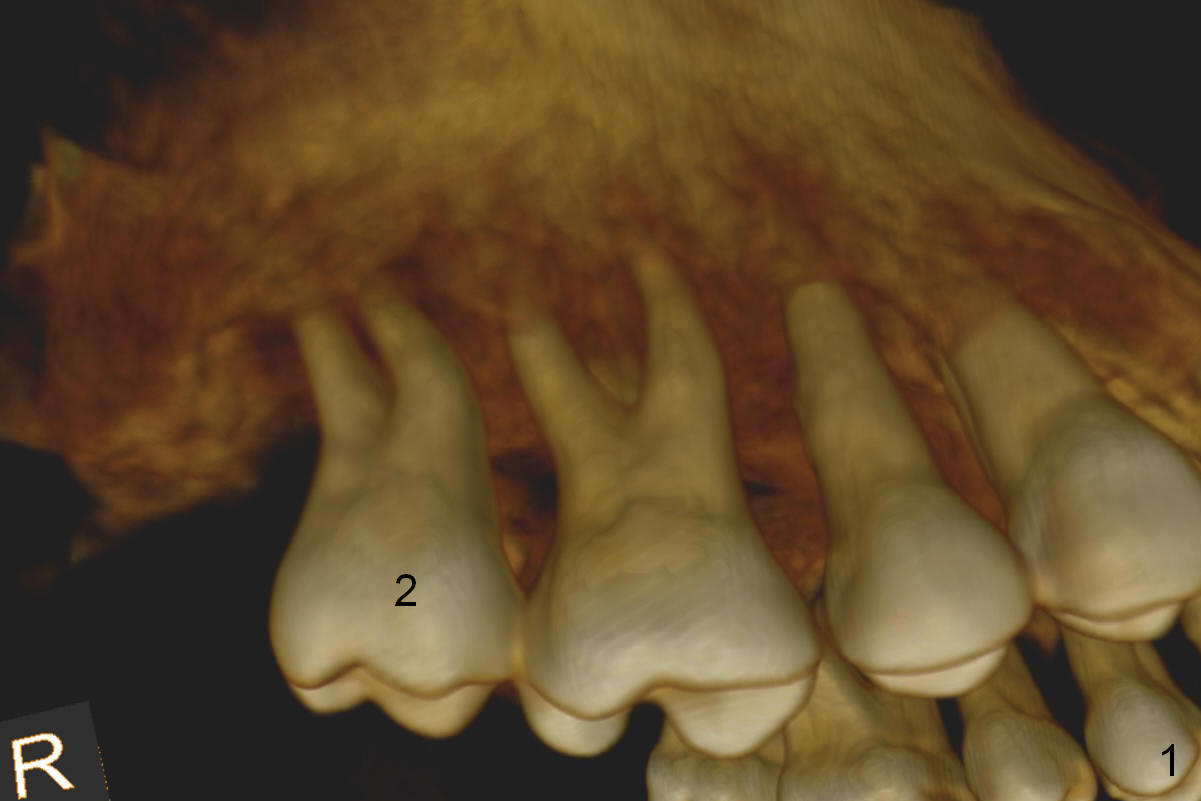

A 46-year-old lady is a typical dental phobic, but she is reasonable. Her chronic periodontitis is generalized and severe (Fig.1 3-D image, taken 1 year ago). An implant has been placed at #6 (healed site). It fails for the first time, probably due to bone loss after extraction. Soon after last periodontal maintenance, the tooth #2 develops pain and swelling. Immediate implant is a must.

The socket is wider buccopalatally (Fig.2 (3-D disto-occlusal view),3 (coronal section)) than mesiodistally (Fig.1,4 (sagittal section),5 (axial section)). Unless more bone loss has occurred in the last year, a 6x10 mm UF implant is to be placed in the middle of the socket (Fig.6, (soaked with 2% Xylocaine/1:50,000 Epinephrine gauze)) with bone graft to be placed in the buccal and palatal gaps (red circles). Bone density in the middle of the socket is 550-700 Hounsfield units. Use RT2 or 2 mm pilot drill to start osteotomy ~ 3 mm. The largest osteotome is RT4, or largest reamer 4 mm, followed by 4.5x17 mm tap at 14 mm, until 6x17 mm one. Make sure that the sinus floor is penetrated.